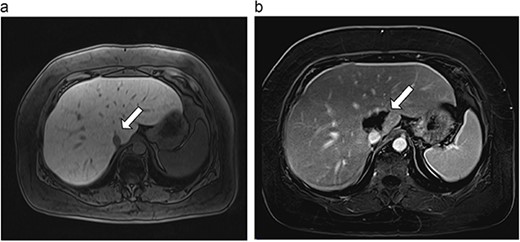

Six patients with six primary or secondary tumors of the caudate lobe were identified (Table 1). Median age at diagnosis was 68 years (51–77 years); two patients were female. Primary disease process was colon adenocarcinoma (n = 4; Figs 3–6), hepatocellular carcinoma (HCC; n = 1; Fig. 7) and metastatic pancreatic neuroendocrine tumor (n = 1; Fig. 8). All patients with colon adenocarcinoma received systemic therapy with 5-fluorouracil, oxaliplatin, and leucovorin (FOLFOX) prior to microwave ablation of hepatic metastases. The patient with metastatic neuroendocrine tumor had progression of hepatic metastases on lanreotide prior to microwave ablation. The patient with HCC had previously been treated with transarterial embolization and cryoablation of tumors, but had recurrence of disease, which was managed with microwave ablation.

| 2 (4a,b) | 67, M | Colon adenocarcinoma | 8 cycles capecitabine and oxaliplatin | 6 | Laparoscopic microwave ablation | 15 | 35 | 20 | 6 | No |

(a) Pre-ablation MRI demonstrating 15 mm lesion in caudate lobe of liver (image degraded by motion artifact). (b) Post-ablation MRI (20 days postoperatively) demonstrating 35 mm complete ablation of caudate lesion (image degraded by motion artifact).